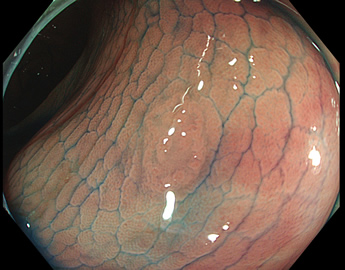

TXIは、「画像の構造を強調する」技術です。これは特別に目新しいものではありません。パソコンの画像編集ソフトや、スマホのアプリでも御馴染みの技術です。しかし、「どのような構造強調が実際に、内視鏡に一番、合うか?(強すぎると不自然になる!)」は、難しい(アナログ的な)課題です。オリンパス社は数タイプのTXIモードを用意しました。半年間の試行錯誤の末、今では下記のモードがベストと判断しました。そして今では「TXI無しの内視鏡は不要(フルタイムTXI)」というまで常用しています。

以下に実例を挙げます

写真だけ、見ると「言われてみるとTXIの方が認識しやすい。でも僅かの差」と感じるでしょうが、この「僅かの差」が、人間の脳での検出には大きな差になります。青い色素(インジゴ・カルミン)が非常に強調され、粘膜の凸凹が明瞭になるのが特徴です。

通常観察 TXIモード